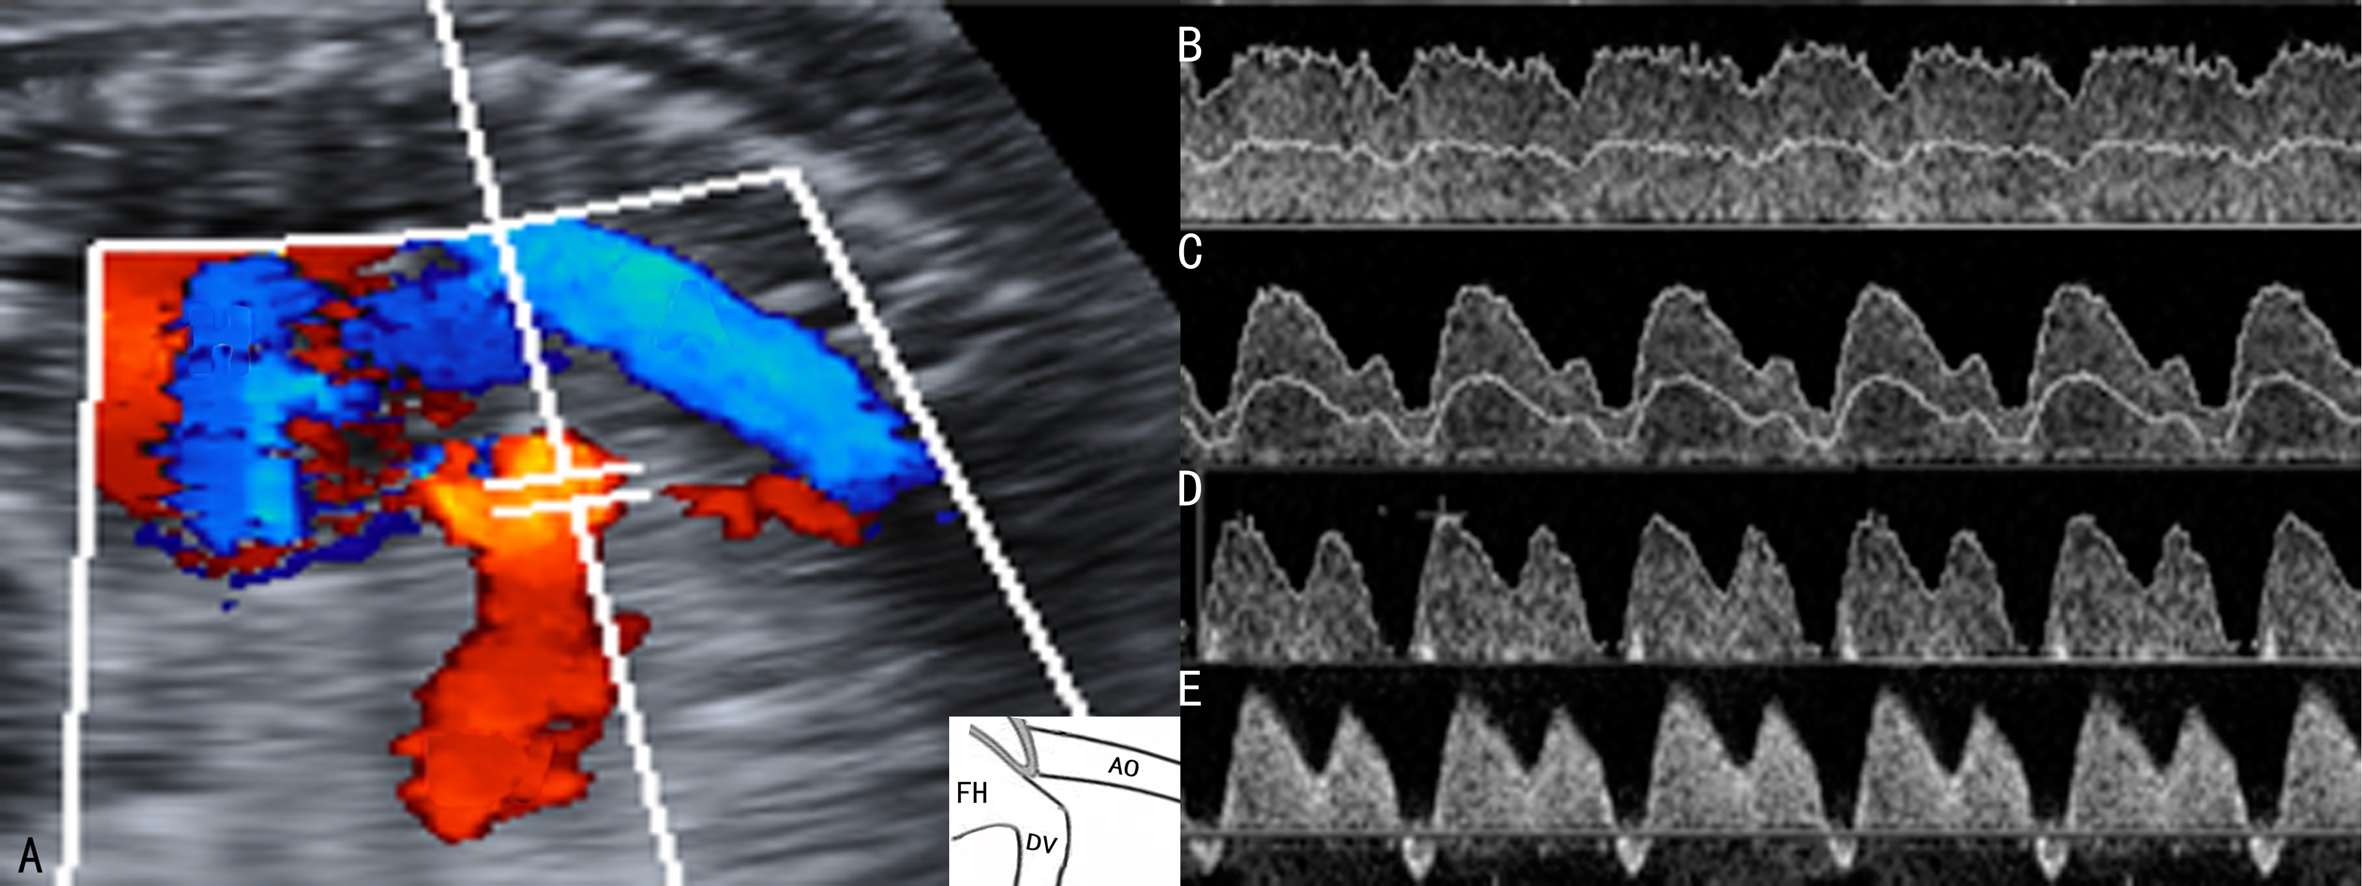

FGR时胎儿右心的血流动力学改变早于左心,舒张期早于收缩期,与右心舒张功能密切关联的静脉导管血流频谱可以很好地反映这种变化(图3),Va降低(图3C)、消失(图3D)或反向(图3E)是心房收缩期前向性血流降低的直接证据,同时还可发现,DVRI和DVS/A升高,且DVRI、DVPI和DVS/A越高胎儿预后越差;严重的FGR时胎儿心功能严重受损,心输出量下降,中心静脉压增高,DVa出现反向,提示胎儿缺氧已无法代偿并已经发生右心功能衰竭,多需要立即处理或终止妊娠。模拟实验提示在发育受限的胎儿中静脉导管明显扩张,其直接后果就是有更多的血流流向胎儿的大脑和心肌以保证其血流供应。在FUA血流没有明显异常的FGR胎儿中,DV的血流与正常胎儿比较无明显差异,但在严重的胎盘血流灌注异常时,DV的血流增多比较明显而流向肝脏的血流减少;FUA PI超过95th百分位、舒张末期血流消失或反向时,DV血流更是明显增加。

图3 FGR时静脉导管血流速度曲线变化

A:静脉导管CDFI显示

B:正常静脉导管血流速度曲线

C:静脉导管血流速度曲线显示舒张期血流速度降低

D:静脉导管血流速度曲线显示舒张期血流消失

E:静脉导管血流速度曲线显示舒张期血流反向流动